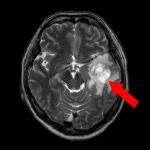

No.’25_26 手術前1

No.’25_26 手術前2